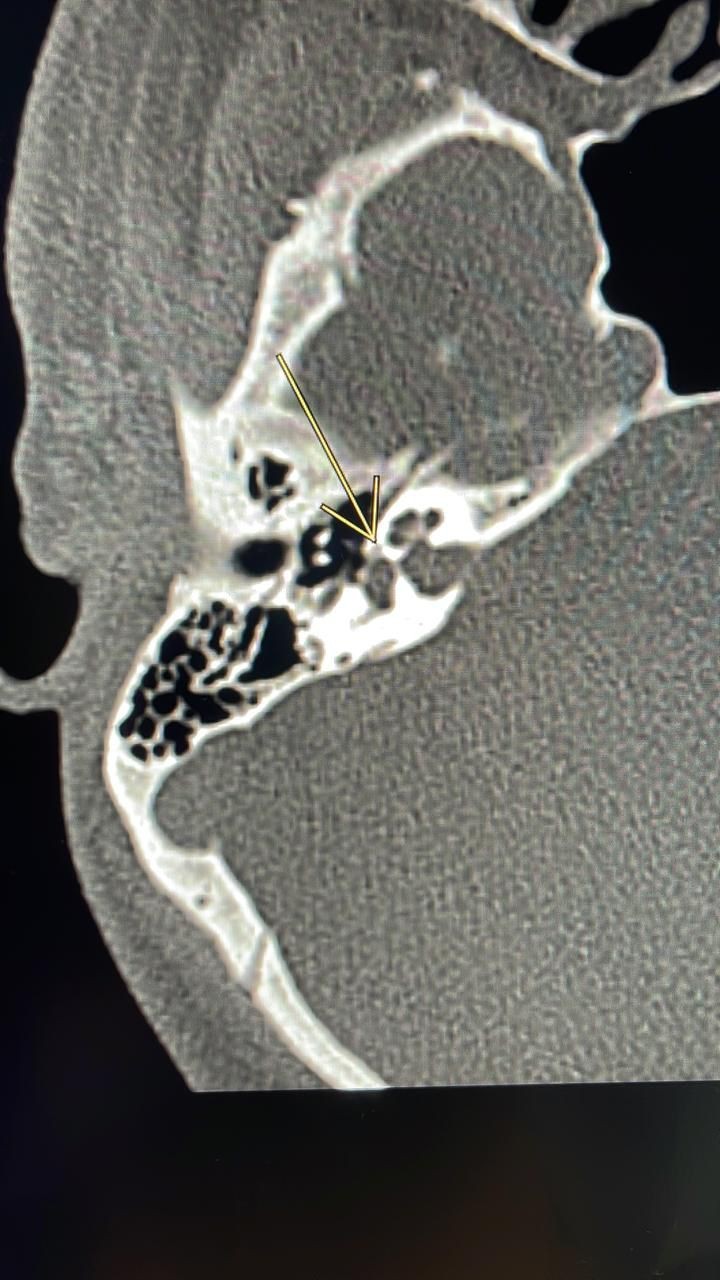

واستقبلت المدينة الطبية المريض الذي كان يعاني من ضعف في السمع وتم إجراء كامل الفحوصات الطبية اللازمة والتي أظهرت نتائجها وجود تصلب عظمة الركاب والذي تسبب بانعدام وجود الاهتزازات التي تنقل الصوت نتيجة نمو العظم حول الصفيحة القدمية لعظمة الركاب مما يتسبب في فقدان تدريجي للسمع.

وأوضح الدكتور فارس الغامدي بأن عملية ثقب عظمة الركاب بالمايكروسكوب هي عملية جراحية يتم فيها إصلاح فقدان السمع التوصيلي الناتج عن تصلب عظام الأذن الوسطى حيث تصبح عظمة الركاب متصلبة وبذلك لا يمكنها الاهتزاز نتيجة نمو العظم حول الصفيحة القدمية لعظمة الركاب ويتسبب ذلك في فقدان تدريجي للسمع، وأضاف بأن عملية ثقب عظمة الركاب تساعد في علاج تصلب الأذن الوسطى عن طريق تجاوز عظمة الركاب المتصلبة بأخرى صناعية.